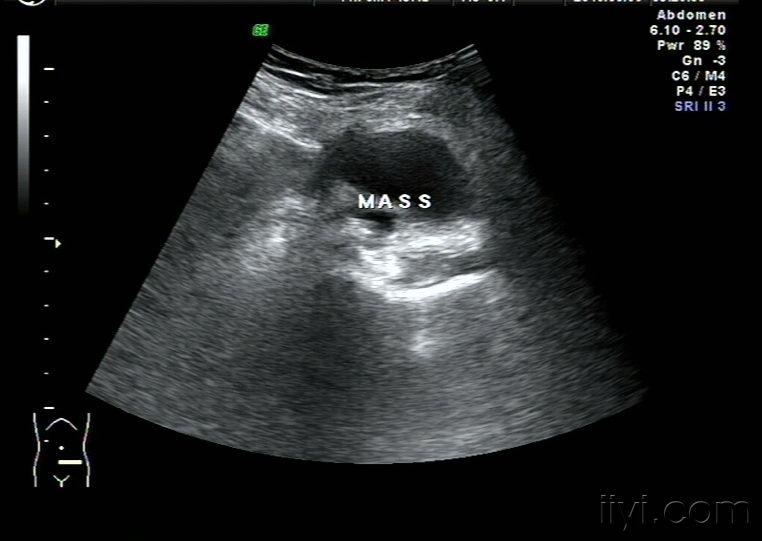

囊肿和实质性肿块的声像图比较 肝囊肿 肝肿瘤